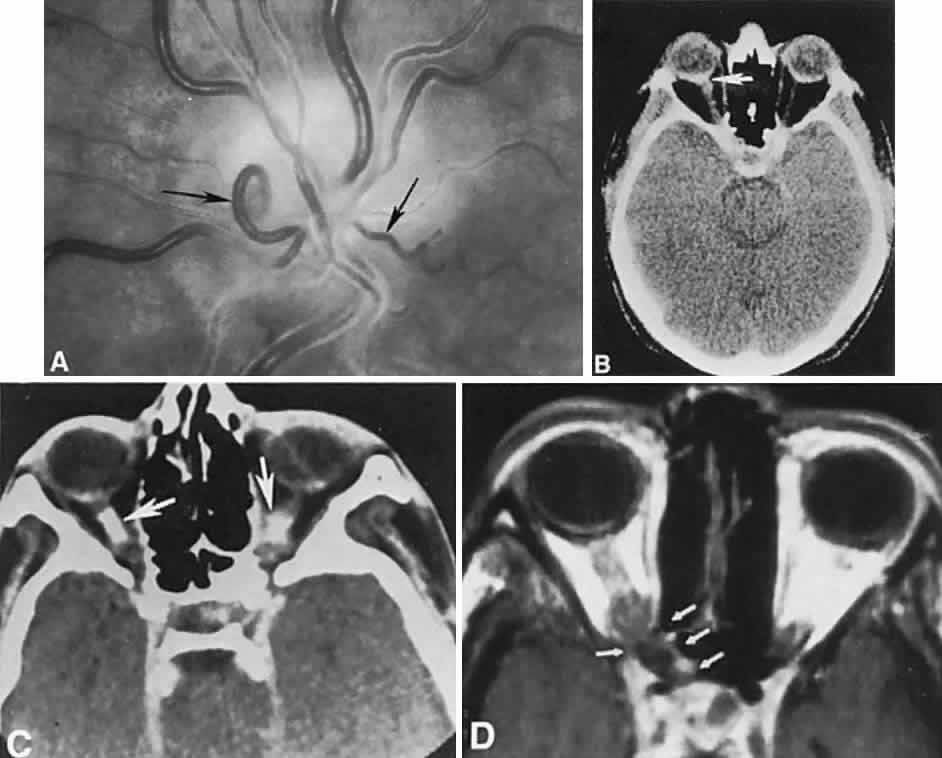

With acute infarction, the retina becomes opaque and takes on a creamy or gray appearance. Atheromatous material in the form of “bright plaques” of cholesterol or other microemboli may be seen, especially lodged at arterial bifurcations (Fig. 5). Segmental arteriolar mural opacification (see Fig. 5D) may follow retinal microembolization by weeks to months, and such sheathing may be as useful as the recognition of the cholesterol embolus itself.43 ERG may show diminished B-wave amplitude, a finding indicating inner retinal ischemia. Weeks following retinal infarction, the optic disc becomes pale, and the arterial tree becomes narrowed in the sector corresponding to the arterial occlusion.

Fig. 5. Retinal microembolic phenomena. A. Bright cholesterol plaque (arrow) impacted at an arterial bifurcation. Thin crystal does not obstruct flow. B. Cholesterol crystals in disc vessels (arrows). Often, the plaque appears larger than the vessel diameter. C. Infarcted opaque retina. The artery contains emboli (? fibrin platelets) that have obstructed flow. D. Reactive opacification of the arterial wall. Fluorescein angiography demonstrated flow through this formerly occluded vessel.